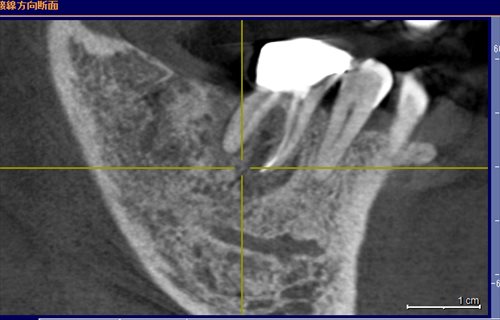

初診のレントゲン:歯の根っこの回りの黒いところはすべて膿。そりゃーお父さん揺れますよ、咬めませんよ。。。。。

本日。黒い所の変化に注目です!!骨の再生が!揺れもなくなり噛めるとの事。鯵を頭から食べたいと今日しきりに言っていました。まだまだ安定とはいえませんが治癒傾向である事は確かだと思います。